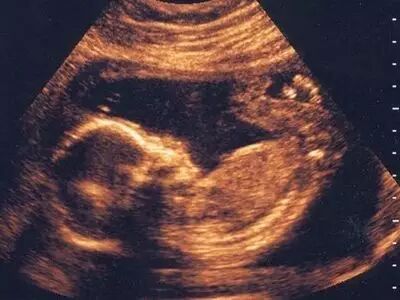

大多数妈妈都不喜欢讨论这个话题,但不少争论的事实是许多男婴在子宫里都会犯错。研讨发现,男女婴儿在子宫内都可能有手淫的举措,超声波图像也曾抓拍到男婴的勃起图片。不过只有男性能在X光片上看出来,原因嘛…你们懂的。